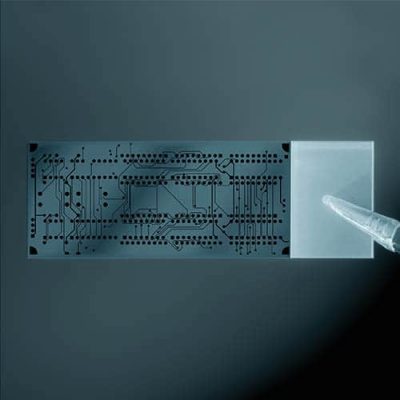

Diagnostic in vitro des microstructures

Sur les composants moulés par injection pour le diagnostic in vitro (PCR numérique), nous utilisons notre microscope à grande vitesse pour tester les fermetures de conduits, les structures de conduits, la perméabilité, les points de remplissage, les défauts, l'entrée de particules et l'uniformité jusqu'à 1 million de points de test par composant .